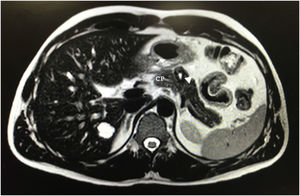

Tras 10 meses de seguimiento, en la RM abdominal se objetivó una lesión en el cuerpo pancreático de 20×18×17mm, hiperintensa en T2, sugestivo de componente cístico vs. necrosis central, con una discreta hipointensidad en la periferia con realce progresivo en la fase portal y tardía (fig. 1). Dada la presencia de componente sólido no se podía descartar malignidad. Sospechando un tumor neuroendocrino se solicitó un Octreoscan que resultó normal.

En RM el contorno es regular, con límites bien definidos en T2. La intensidad del interior de la lesión es ligeramente heterogénea, hipointensa en T1 e iso o hiperintensa en T25,7,9.

Algunos autores sugieren que se debería realizar cirugía conservadora para preservar la integridad del tracto gastrointestinal y la función endocrina y exocrina del páncreas, así como la esplénica, por la naturaleza indolente de este tumor7. Nosotros optamos por PD con preservación esplénica debido a la sospecha inicial, desaconsejando la realización de cirugía preservadora de parénquima por el riesgo de fístula, dada la relación de vecindad del tumor con el conducto pancreático principal (fig. 1).